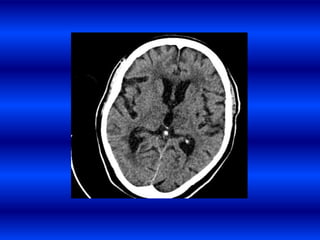

Causas de la HI en pacientes hipertensos.

• Lipohialinosis de las pequeñas arterias

intracerebrales.

• Microaneurismas de Charcot y Bouchard.

Localizaciones mas frecuentes de la HI

1. Putamen (35%).

2. Lobular (25%)

3. Tálamo (10-15%).

4. Cerebelo (5-10%).

5. Protuberancia (5%).

• 32.

Causas de laHI en pacientes hipertensos. • Lipohialinosis de las pequeñas arterias intracerebrales. • Microaneurismas de Charcot y Bouchard.

• 33.

Localizaciones mas frecuentesde la HI 1. Putamen (35%). 2. Lobular (25%) 3. Tálamo (10-15%). 4. Cerebelo (5-10%). 5. Protuberancia (5%).